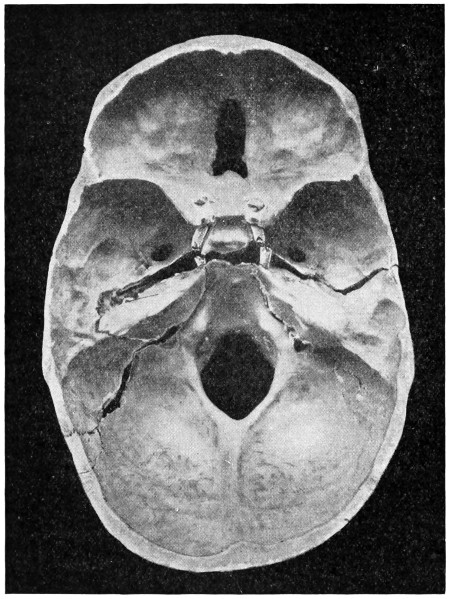

29 A and B. The base of the skull and the base as seen on transillumination 70, 71

50 A and B. The inner aspect of the skull and the same seen on transillumination 137